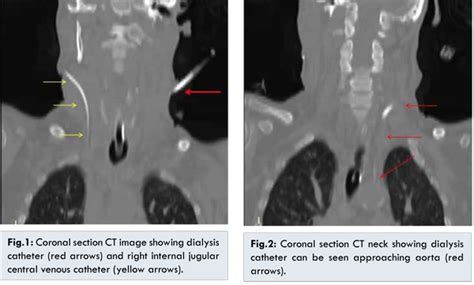

Vertebral Artery Injury with Dialysis Catheter